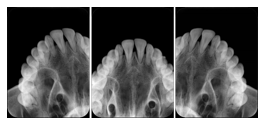

2. A patient requests cosmetic surgery to enhance their facial appearance. The case requires consultation between an orthodontist in New York and an oral surgeon in California. The cephalometric series of 2D projections constructed from a volumetric CT data set that is used for the discussion is arranged by a Structured Display for transfer between the two practitioners.

Cephalometric Series Structured Display

Figure OO-2. Cephalometric Series Structured Display